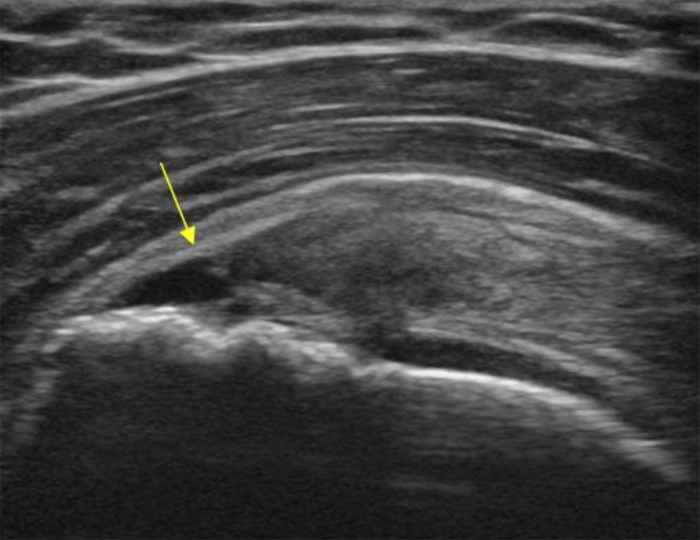

Ultrasound-guided injections have revolutionized pain diagnosis and treatment. Before ultrasound, the vast array of soft tissue pain generators were challenging to diagnose with accuracy, and hard to treat. Now we can precisely target muscles, tendons, joints, and ligaments in a way we never could before. This makes it possible to accurately diagnose even the tiniest pain generators in the soft tissues. Treatment is now far more effective. What used to take multiple visits can now be accomplished in one. It's truly revolutionary.

Lots of patients come to us unable to tell more about their pain other than the location. "It hurts right...there!" This could be a spot near their elbow, over their shoulder blade, buttock, hip, or knee. Sometimes it's just a seemingly random spot on their foot. These "small" pain problems can arise anywhere. Using carefully guided injection therapy, we can accurately diagnose and treat the tiniest of pain generators. It's not uncommon for patients to suffer for years with problems like these, unable to find relief because conventional medicine just doesn't have the tools. Now we do, and with 10 years of experience diagnosing and treating these small pain generators, Dr. Littlejohn can help finally move your care forward.